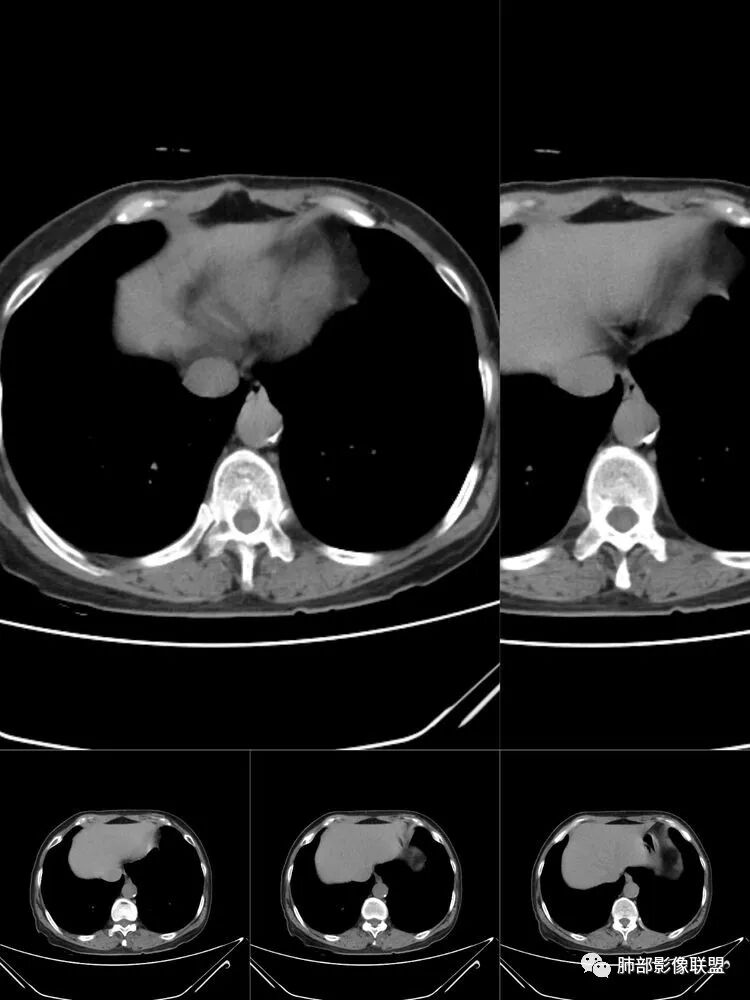

患者,女,64岁,反复咳嗽、咳痰、胸闷10年,加重2周患者10余年来每当受凉感冒出现咳嗽、咳痰、胸闷,有时痰中带血,输液治疗(具体不详)可好转。既往有声带肥厚手术病史。CT示气管、主支气管及分支支气管管壁弥漫性增厚累及膜部,局部伴钙化,管腔狭窄,考虑淀粉样变性

患者,女,64岁,反复咳嗽、咳痰、胸闷10年,加重2周。气管支气管及两肺下叶 支气管弥漫性的环状增厚,管腔扩张,管腔感觉比较松弛。第一感觉,气管支气管淀粉样变。鉴别诊断,1、支气管内膜结核,肺内散在一些支气管的播散病灶,粟粒结节为主,形态比较单一。2、复发性的多软骨炎,就得了解一下其他部位,有没有多个部位的软骨炎。这个病人右侧胸廓缩小,升主动脉明显的扩张,其横径明显的超过了降主动脉。

南边:肺部有肺气肿支气管腔狭窄淀粉样变性?复发性多软骨炎?血管炎?慢支?结核?曲霉菌?南边:一般还是淀粉样变性与复发性多软骨炎鉴别其次就是支气管骨化症,但是骨化下朝上,且壁结节状钙化明显,本例不太支持。至于结核、曲霉菌?1.结核,一般不会这么广泛,支气管壁狭窄后扩张2.曲霉菌可以这么广泛,但是支气管壁管腔扩张,而且附近脂肪间隙有炎性反应,不太支持;3.血管炎,一般合并肺内有病灶,但是声带受累,放待排;4.软骨炎一般全身受累,例如耳廓等;而且膜部不受累,不太支持;倾向于淀粉样变性;淀粉分很多型,气管支气管是最常见的。尘缘:影像上生理性钙化与支气管骨化无法区别,镜检也不好鉴别,需要依赖活检,看粘膜中是否合并炎性改变(淋巴细胞,组织细胞等炎性细胞侵润)来鉴别Coke with ice:经常看到的这种是老年性肺改变,又称年龄相关肺改变。气管和支气管弥漫性软骨钙化,常见老年女性。尘缘:支气管骨化症很罕见的,所以绝大多数还是生理性钙化。对于老年人,无临床症状的钙化,还是基本上都是生理性钙化,无临床意义。大雄:如果管壁钙化伴明显增厚 影像还是提示一下建议支气管镜稳妥些

病理结果:肺淀粉样变

气管支气管淀粉样变性

三、影像表现

1.气管支气管型

①气管支气管壁增厚,形成粘膜下斑块与结节

②管腔广泛狭窄、闭塞

③管壁钙化

④膜部受累(具有重要鉴别意义)